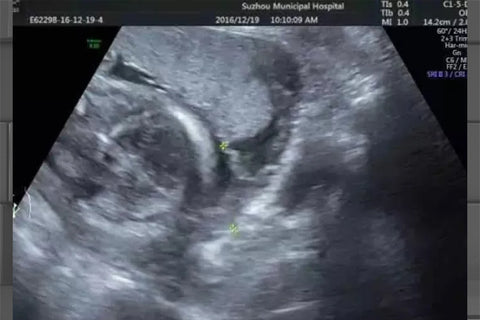

Entonces, ¿cuál es la distancia desde el borde inferior del sinusoide sanguíneo hasta la abertura cervical interna? ¿O medir la distancia entre la placenta y el cuello uterino interno? ¡Creo que es lo primero! Para estar seguro, es más confiable medir a partir de los sinusoides sanguíneos. La imagen es el método incorrecto, discútalo con sus colegas.